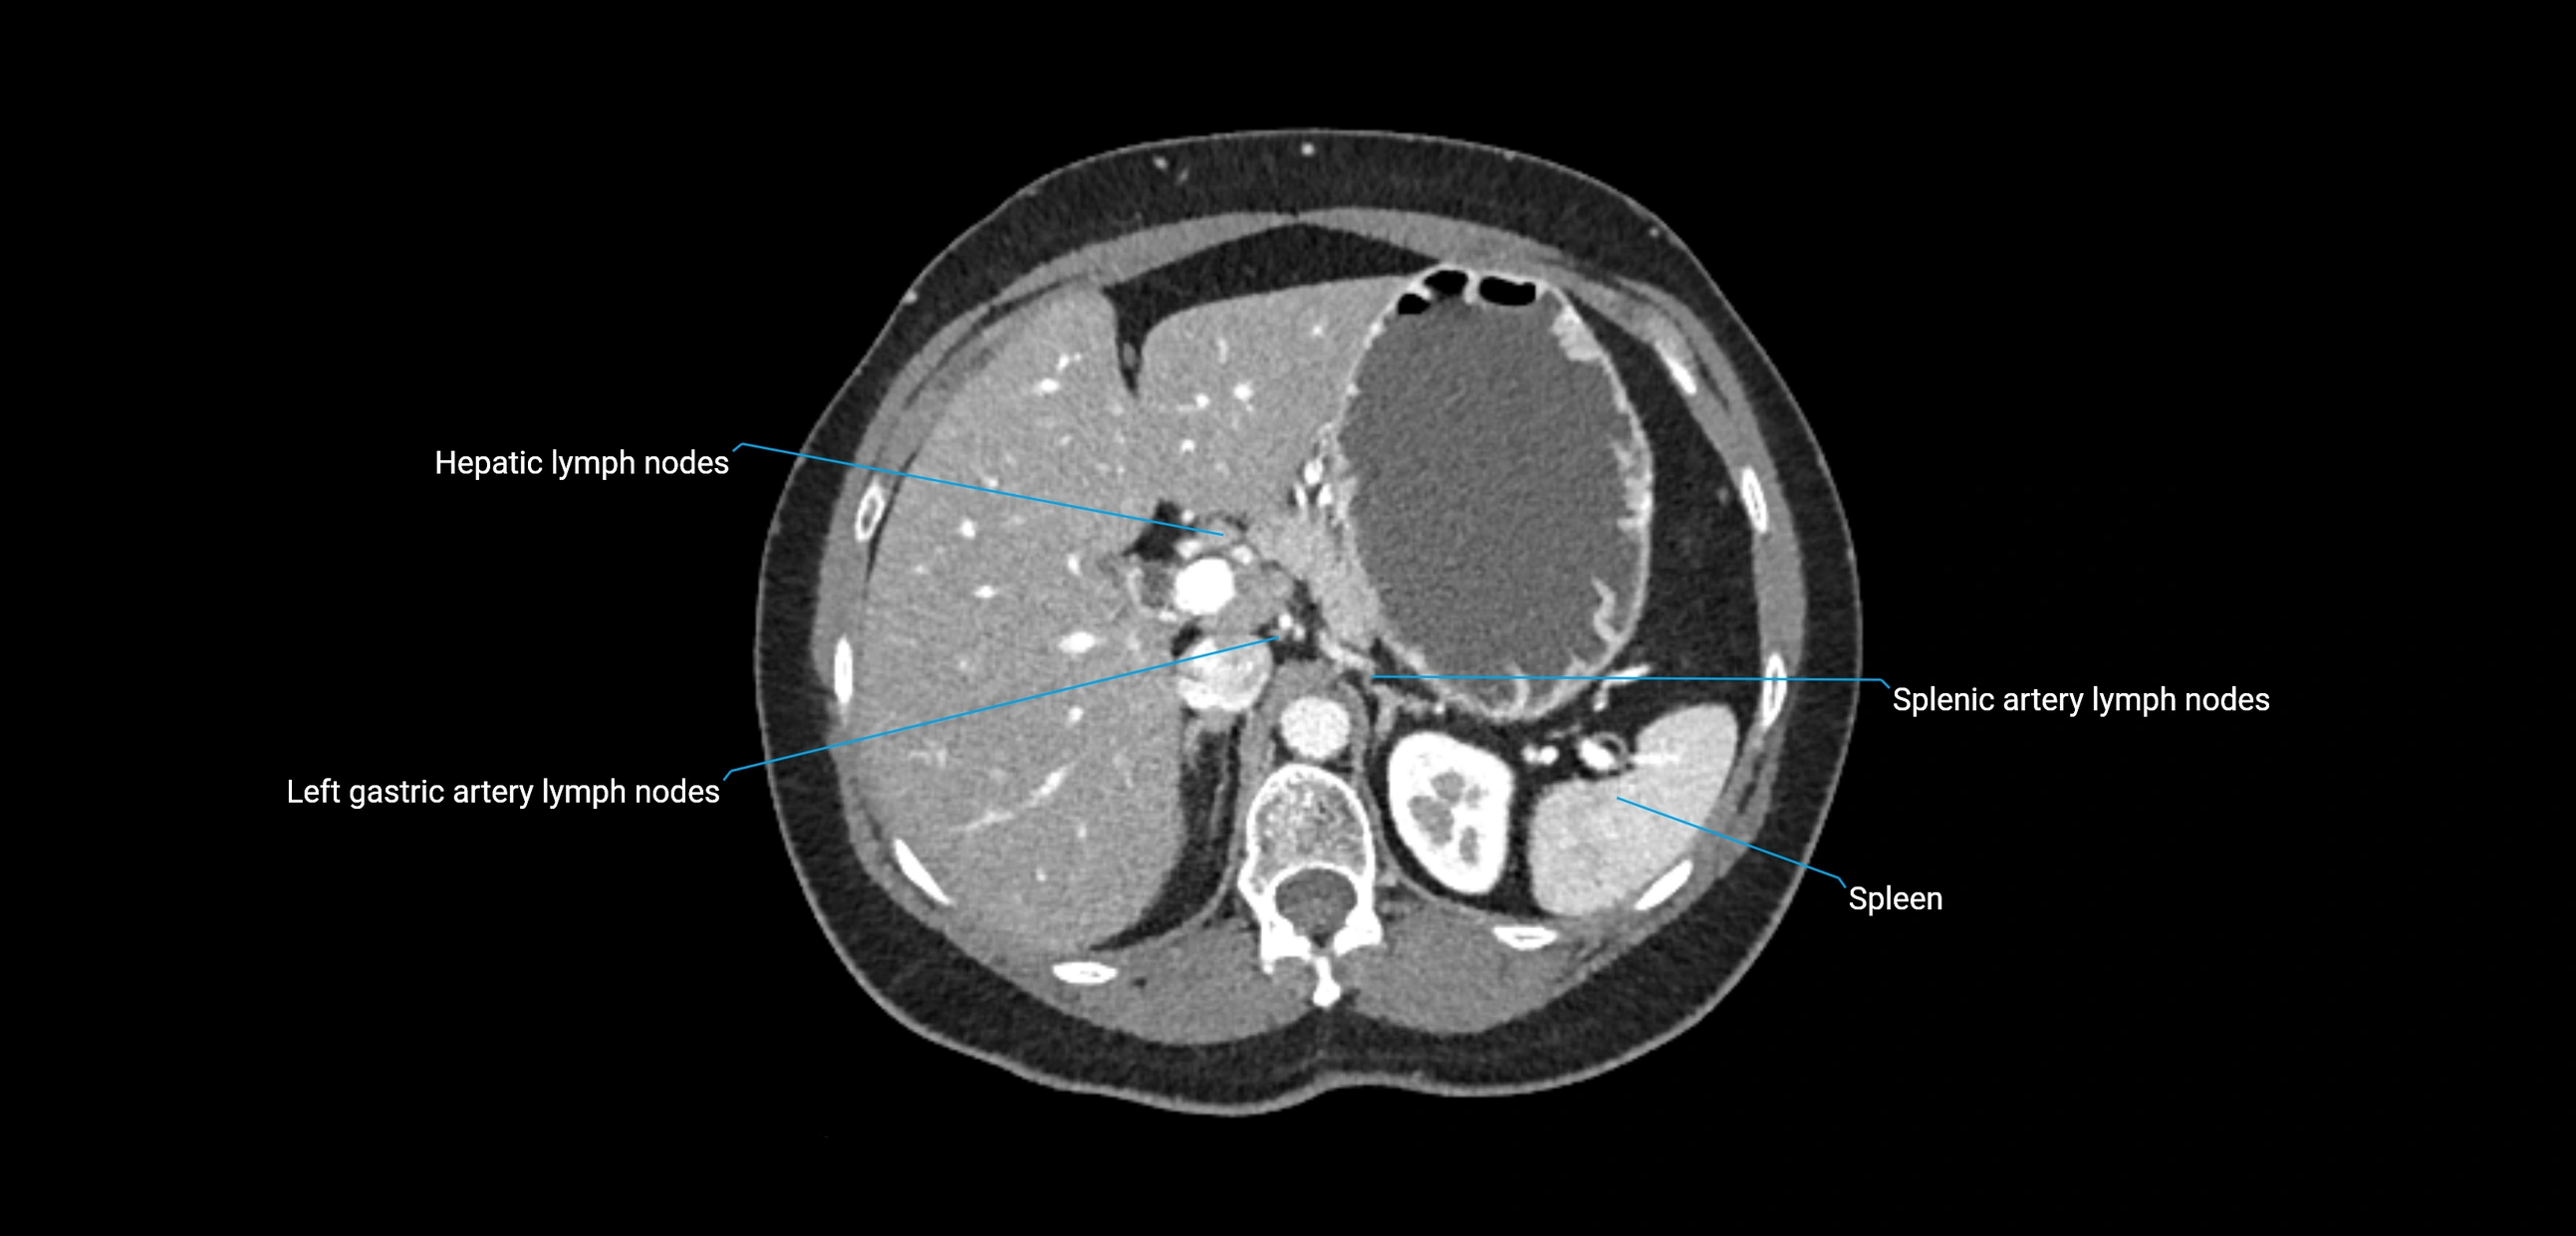

CT Appearance

CT Pre-Contrast:

• Nodes appear as soft-tissue density nodules adjacent to the aorta and IVC

• Calcification may be seen in chronic infections (e.g., tuberculosis)

CT Post-Contrast:

• Normal nodes enhance homogeneously

• Malignant nodes may show heterogeneous enhancement, central necrosis, or conglomerate formation

• Size >1 cm short axis is suspicious, though morphology and distribution are equally important